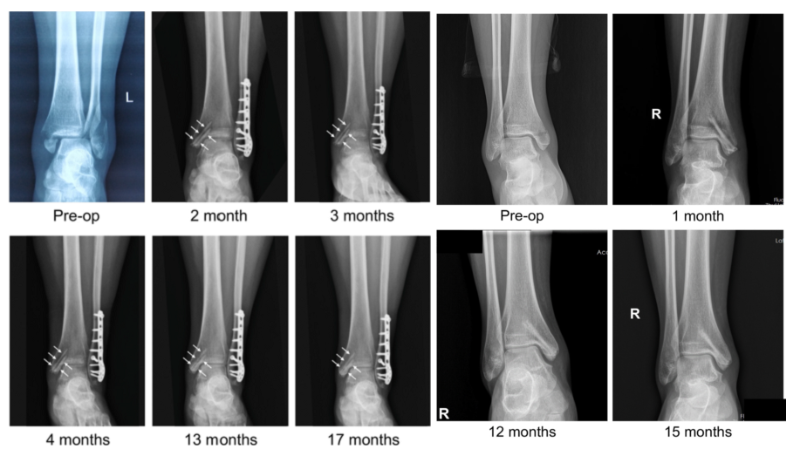

近日,國際骨科臨床轉(zhuǎn)化期刊《Journal of Orthopaedic Translation》在線發(fā)表了由上海交大戴尅戎院士、郝永強(qiáng)教授團(tuán)隊(duì)和丁文江院士、袁廣銀教授團(tuán)隊(duì)合作發(fā)表的可降解鎂合金骨釘1-2年的臨床試驗(yàn)觀察結(jié)果,所有患者術(shù)后內(nèi)踝骨折愈合,功能恢復(fù)。研究證實(shí)了可降解鎂合金螺釘治療內(nèi)踝骨折的臨床療效及其生物安全性,為全降解鎂合金植入物等高端醫(yī)療器械進(jìn)一步的臨床推廣應(yīng)用奠定了堅(jiān)實(shí)基礎(chǔ),相關(guān)成果以“Effectiveness and safety of biodegradable Mg-Nd-Zn-Zr alloy screws for the treatment of medial malleolar fractures”為題在線發(fā)表于Journal of Orthopaedic Translation,27 (2021) 96–100。這是國內(nèi)首個(gè)可降解醫(yī)用鎂合金臨床試驗(yàn)的公開報(bào)道,也是國際首款含有功能涂層的可降解鎂合金骨釘?shù)呐R床試驗(yàn)結(jié)果的公開報(bào)道,具有里程碑意義。

醫(yī)用鎂合金骨內(nèi)植物臨床試驗(yàn)研究突破性進(jìn)展(圖1)